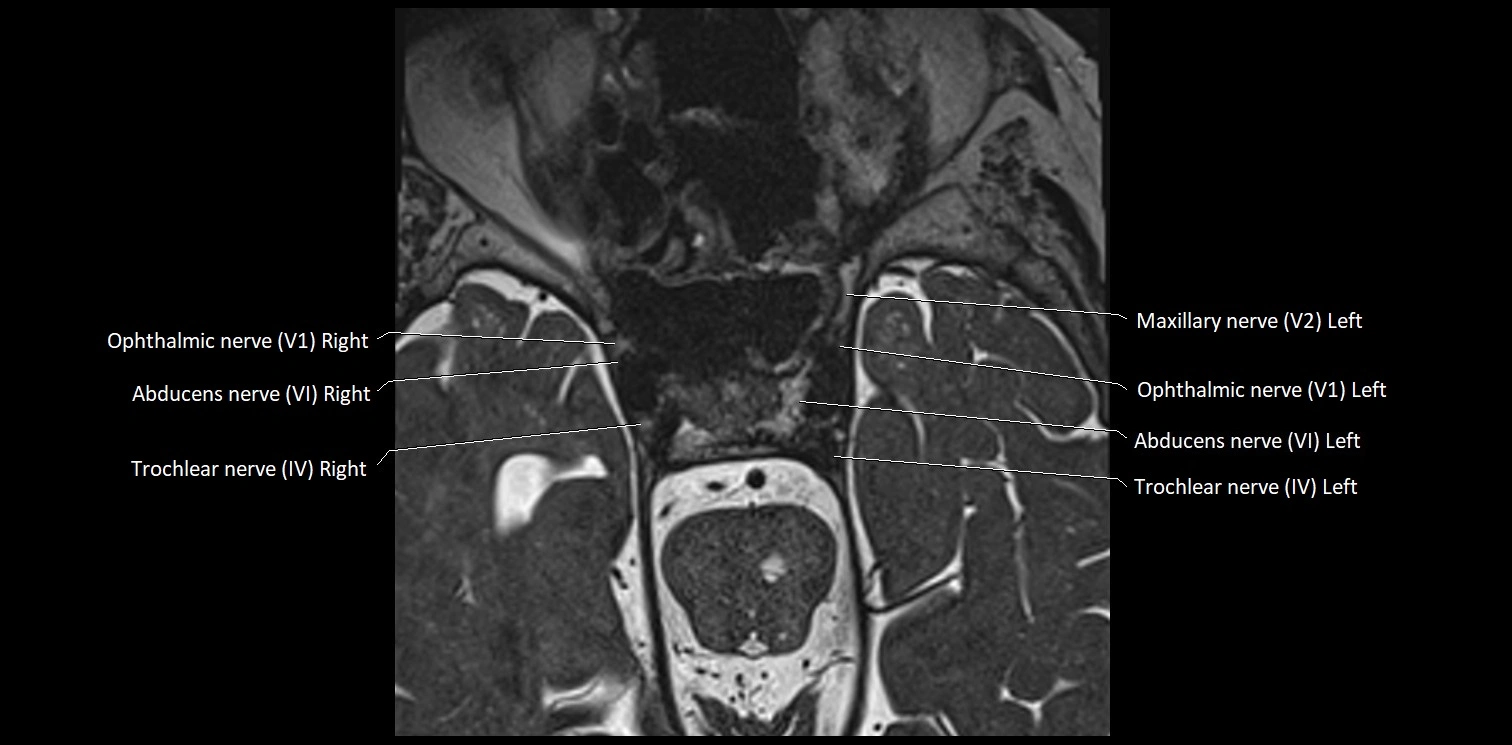

Abducens nerve (Cranial nerve VI)

The Abducens nerve (Cranial nerve VI) is a purely motor cranial nerve responsible for innervating the lateral rectus muscle of the eye, which is crucial for lateral movement (abduction) of the eyeball. It arises from the abducens nucleus in the dorsal pons, emerges at the pontomedullary junction, and travels a long intracranial course before entering the orbit via the superior orbital fissure. Because of its long path and proximity to the clivus, it is particularly susceptible to injury from increased intracranial pressure or trauma.

MRI Appearance

• The abducens nerve is a small, thin, linear structure

• Best visualized on high-resolution T2-weighted 3D MRI sequences (e.g., FIESTA or CISS)

• Seen as a hypointense (dark) line running from the brainstem at the pontomedullary junction, traversing the prepontine cistern, and entering Dorello’s canal under the petrosphenoidal ligament, then into the cavernous sinus, and finally the orbit

• May be challenging to visualize in standard MRI due to its small size

• Pathology may be inferred by absence, displacement, or enhancement of the nerve

MRI images

image